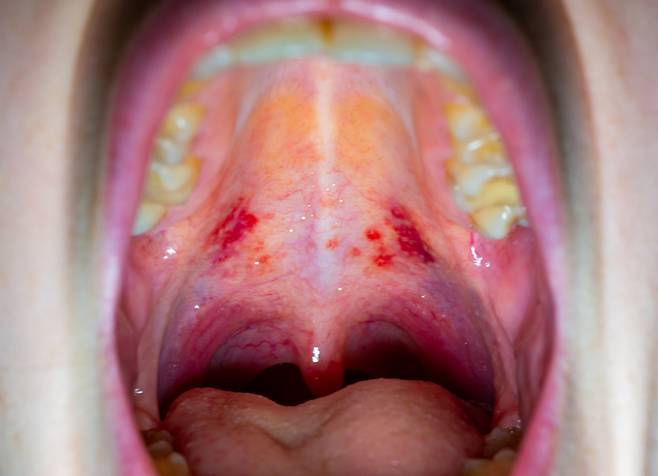

두경부암의 대표적인 원인은 '흡연'과 '음주'다. 특히 구강·인두·후두는 흡연·음주의 양·기간에 따라 암 발병률이 증가한다는 점이 여러 연구에서 확인됐다. 최근에는 성관계를 통해 전파되는 인유두종바이러스(HPV)가 추가적인 주요 원인으로 밝혀졌다. 특히 편도·혀뿌리·연구개(물렁한 입천장) 등에 발생하는 인두암에서 HPV가 검출될 비율이 50~80% 나타나며, 이는 HPV와 구인두암의 높은 상관관계를 보여준다.

두경부암은 수술 후에도 후유증이 크게 남을 수 있어 예방이 중요하다. 술·담배를 최대한 멀리하고, 인유두종바이러스(HPV) 백신 접종, 무분별한 성관계를 주의해야 한다. 특히 인두암의 주요 원인은 HPV로, 자궁경부암을 유발하는 바이러스다. 이에 여러 나라에서 여성에 대해서 자궁경부암을 막기 위한 목적으로 예방 접종을 시행해왔다. 하지만 구강성교를 통해서 이 바이러스가 인두로 이동하면 여러 두경부암을 유발하게 된다. 이를 방지하기 위해 여성뿐만 아니라 남성에서도 HPV 백신을 접종하는 게 권고된다.